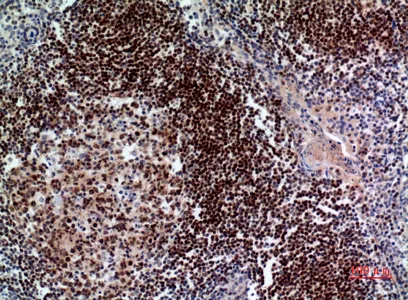

Pax-5 Rabbit Polyclonal Antibody

Cat: APRab15789

Size1:50μl Price1:$128

Size2:100μl Price2:$230

Size3:500μl Price3:$980